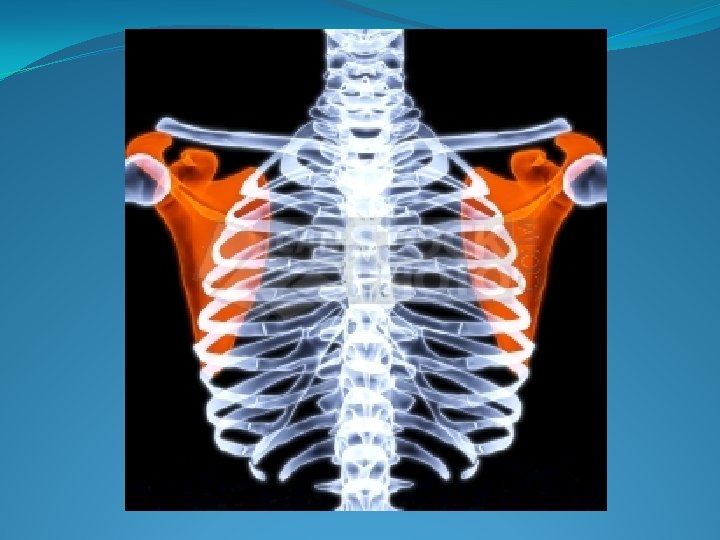

La Jaula Toraxica �Es una estructura osteomuscular, compuesta por las costillas, esternón, las escapulas, músculos intercostales, diafragma. �El diafragma, divide el tórax del abdomen. � El diafragma se inserta en 5 to espacio intercostal (limite anterior). �En la línea axilar media 7 - 8 vo espacio intercostal. �En la línea paravertebral en 12 do espacio intercostal.